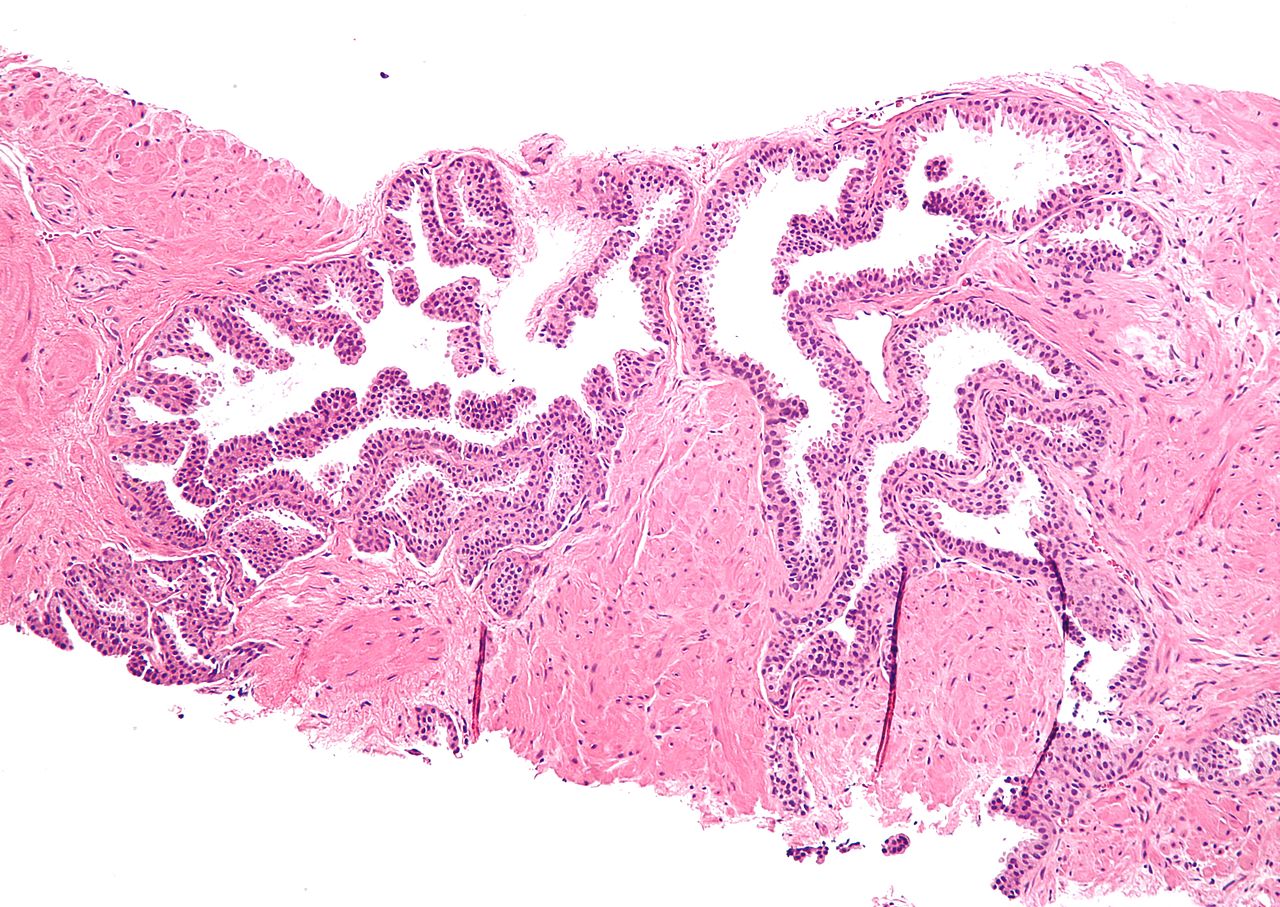

Zorgpad Anale pathologie

Het Zorgpad Anale Pathologie beschrijft de zorg vanaf de verwijzing naar de specialist tot de afspraken van nazorg.

Het Zorgpad Anale Pathologie beschrijft de verwijzing naar de dermatoloog of chirurg in een van de betrokken ziekenhuizen. Op basis van de diagnose zijn de behandelopties uiteengezet.